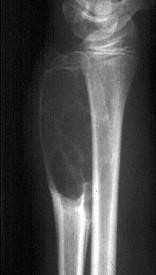

问题 男性,17岁,近2年来感右前臂疼痛,肿胀,2周前由于疼痛加剧,查体右前臂压痛明显,皮肤稍显红肿,请结合所提供图像,选择最佳选项()

选项 A.骨囊肿 B.巨骨细胞瘤 C.动脉瘤样骨囊肿 D.软骨瘤 E.骨血管球瘤

答案 C